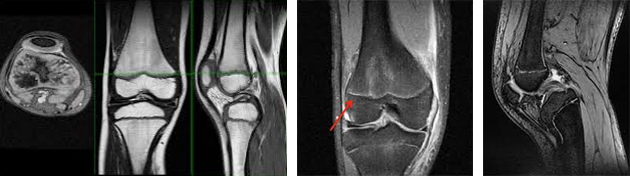

무릎 성장판 MRI (Physeal MRI)모든 검사는 전문의 진료 및 보호자 상담을 통해 개인 상태에 맞추어 선택적으로 진행됩니다.